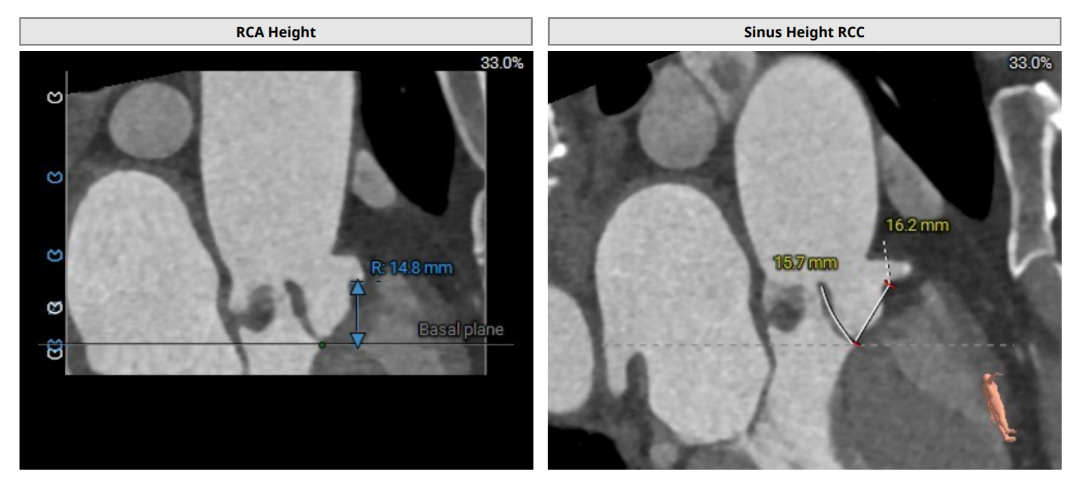

术前评估

术前CT(上下滑动查看更多图片)